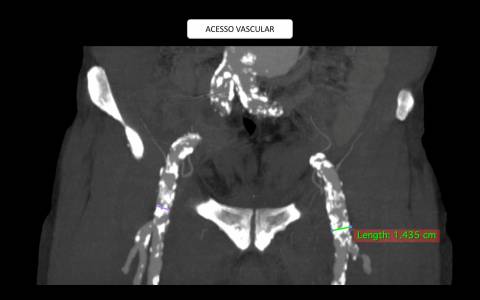

A avaliação por tomografia computadorizada evidenciou um aneurisma infra-renal de colo hostil e acessos vasculares com muita ateromatose. Diante do contexto clínico e de imagem foi optado pelo tratamento endovascular com endoprótese de baixo perfil Incraft CORDIS e técnica de Snorkel Grafts com stents Palmaz CORDIS para as artérias renais.